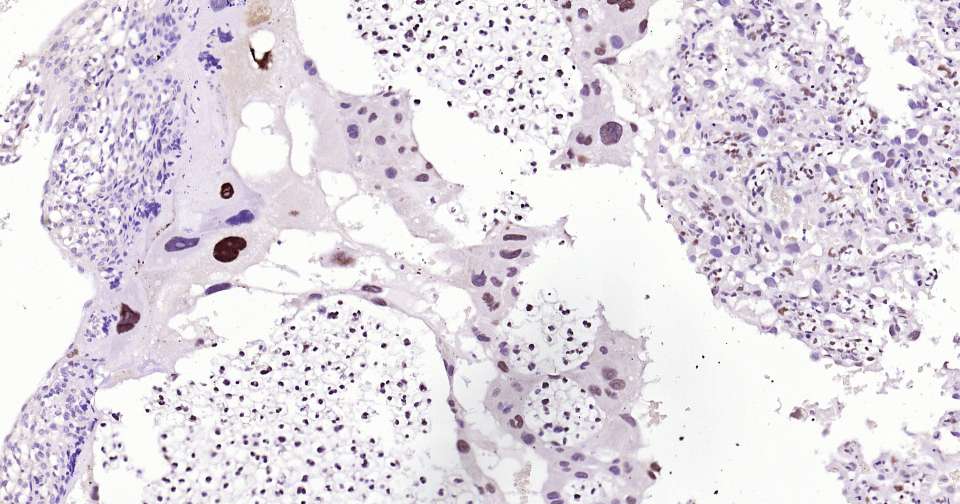

Immunohistochemical analysis of paraffin embedded mouse placenta tissue slide using IHC0337 (Dnmt3a Kit).

Immunohistochemical analysis of paraffin embedded human placenta tissue slide using IHC0337 (Dnmt3a Kit).

Immunohistochemical analysis of paraffin embedded rat placenta tissue slide using IHC0337 (Dnmt3a Kit).